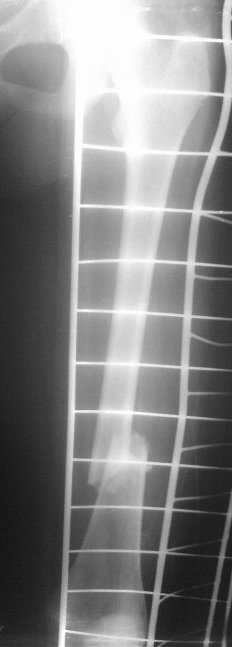

На сегодняшний день вот такая картина: девочка, 13 лет, 3 недели на скелетном вытяжении по поводу оскольчатого перелома нижней трети левого бедра.

Сейчас инфекцию "победили", отек бедра за последние дни значительно спал, но имеется укорочение 2 см, отломки уже "прихватились",патологической подвижности нет.

Да, скелетное вытяжение тут как-то не сработало так как хотелось бы. Груз 6 кг (вес 45 кг). Сейчас уже, видимо, расчитывать на вытяжение не приходится, т.к. мозоль начала формироваться и подвижность исчезла.

Как-то вот совсем бы не хотелось открываться-то. Осколков, там похоже не один, а два как минимум (не совсем хороши снимки). Боюсь, что накостный остеосинтез, даже перкутанный, привяжет пациенку к отделению еще больше. После гнойной лихорадки, мождет и "полыхнуть", так что "мама не горюй". Риск, думаю, сохраняется.

Это снимки при поступлении, похоже.

Я бы сделал свежие. Пока предполагаю, что раз срок большой, возраст маленький, то, вероятно, лучше в два этапа - - аппаратом растянуть за неделю, а потом заштифтовать. Раз старше 12 лет, то согласен с Марком, не TENами, а нетолстым ригидным стержнем с латерализованным проксимальным отделом. Зона роста если и пострадает, то всего одна, и за оставшейся период роста не успеет сформироваться разница длин.